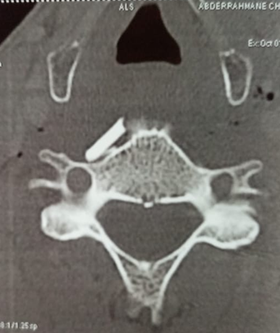

A cervical CT scan with injection of contrast product

was then carried out to assess the lesion and guide the treatment. It revealed

the presence of a prevertebral foreign body, but miraculously all the vascular,

digestive and aerial anatomical structures were intact (Figure 2).

Figure 2: CT scan showing the

presence of a prevertebral foreign body